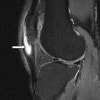

MRI : 호파병(Hoffa’s disease)